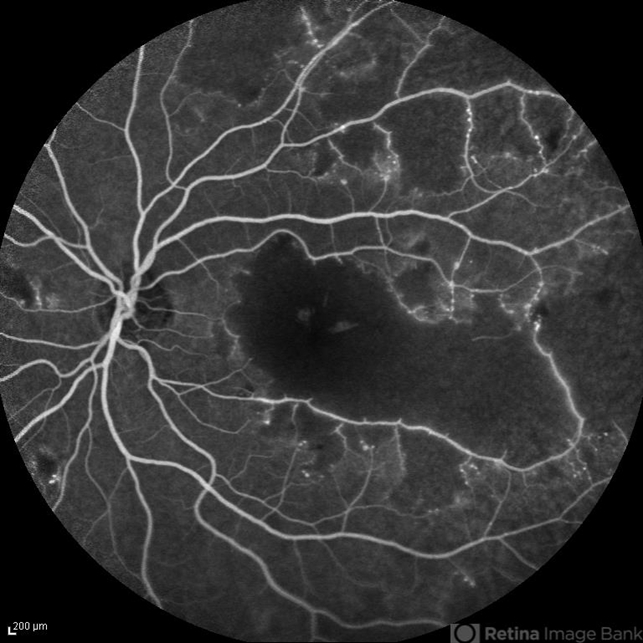

- capillary closure

- Elham Salehi, Negah Eye Center, Tehran

- Heidelberg Spectralis

- Late phase FA image of the left eye of a 28-year-old woman with idiopathic occlusive retinal vasculitis 6 months after the onset.